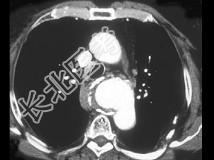

- 单项选择题患者60多岁,男性, 胸部不适加重,最可能的诊断为 ( )

A、食管癌

B、肺癌

C、主动脉瘤破裂

D、淋巴瘤

E、以上都不是